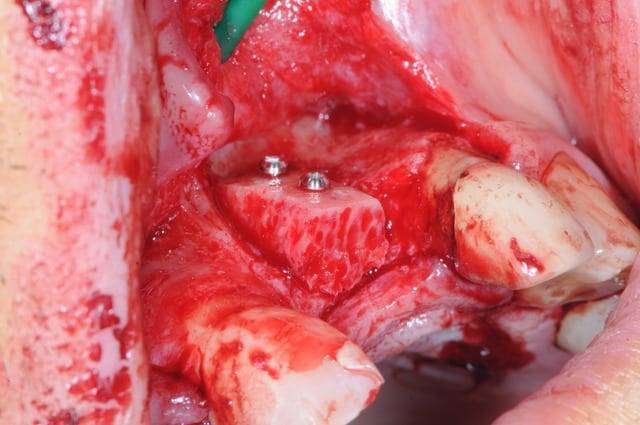

1 :préparartion du lit par un prélèvement avec tréphine

2-3-4 :lit receveur

1-2 : vis d'ostéosynthèse Stoma ; diamètre 1 mm (ceux sont les plus petites du marché)

3 vérification de l'adaptation du greffon au lit receveur

(au moins avec cette technique on a pas beaucoup de travail de préparation...)

4 stabilisation pince stoma

5 greffon en place